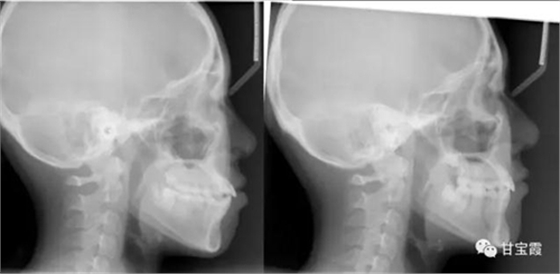

下面的矯正前后的對比照片看出側(cè)貌得到了改善

矯正前后的面相顯示小女孩變得更漂亮了。